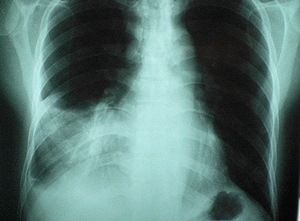

Acute Chest PainChest pain is a common symptom of acute cardiopulmonary disease. The precise location and character of this pain is a very useful diagnostic tool.